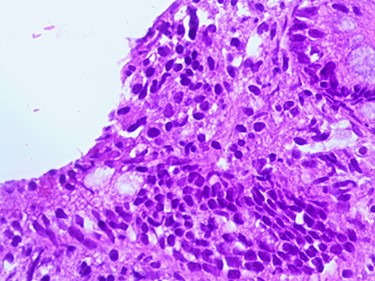

Postoperative ileoileal intussusception after surgical reduction.

A 3.5-year-old Syrian female was admitted to our hospital with complaints of abdominal pain. She had had several episodes of non-bilious, non-bloody vomiting for 36 hours, and her last normal bowel movement was 2 days prior. Although the patient had a history of sickle cell anemia confirmed by electrophoresis from her first year of life, she had not experienced any sickle cell crises and had not needed blood transfusion or hospitalization. She had no history of diarrhea, either. Family history for celiac disease was positive in a second-degree relative. On admission, her vital signs were normal. Blood analysis indicated low hemoglobin (Hgb) concentration of 9.3 g/dl, but other initial laboratory results were normal. Abdominal examination showed tender distended abdomen. Abdominal ultrasonography suggested the presence of intussuscepted bowel in the right iliac fossa with free fluid between the bowels. Hydrostatic reduction (HR) was not successful, so she underwent surgical reduction. Although no lead points were found, there were multiple enlarged mesenteric lymph nodes and edematous ileocecal junction. On the third postoperation day, the patient again developed similar symptoms, and this time ultrasonography revealed IS in the left side of the abdomen. There was no improvement in symptoms for 24 hours, and ultrasonography revealed the same results after an HR attempt. The patient was operated on a second time, and manual ileoileal IS (Fig. 1) reduction and prophylactic appendectomy were performed. The postoperative course was uneventful, and the patient was discharged 3 days later. Three months later, the patient developed abdominal pain, and the diagnosis of IS was confirmed via ultrasonography. This time, IS reduced over 24 hours of observation. As no lead point was found through the later laparotomy, further investigations were conducted. Upper gastrointestinal endoscopy was performed and showed a mosaic pattern of the duodenum mucosa suggestive of CD. On microscopic evaluation, sections reveal advanced atrophy of duodenal villi with occasional intraepithelial lymphocytes (>30/100 IEL). Crypts show moderate hyperplasia; the lamina propria is infiltrated by diffuse mononuclear inflammatory cell infiltrate. Histopathologically, it is compatible with Grade B2 on the new grading system for CD classification (Figs 2–4). The child was then administered with a gluten-free diet. Eight months later, she visited the hospital as outpatient, and examination revealed she was free of any symptoms.